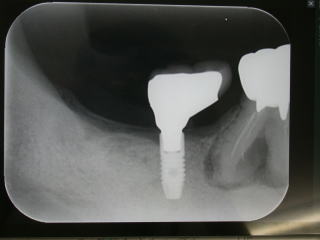

症例10、60才代男性、(新潟県長岡市要町、要町歯科、インプラント)

右下7番の欠損部分にインプラントを植立しました。

インプラント稙立は2018年4月6日。

上部構造物(白い歯)の装着は2019年9月28日です。